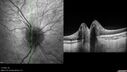

Stable Myopic Tractional Maculopathy32 views73 year old female with mild vision loss from table myopic tractional maculopathy in the left eye